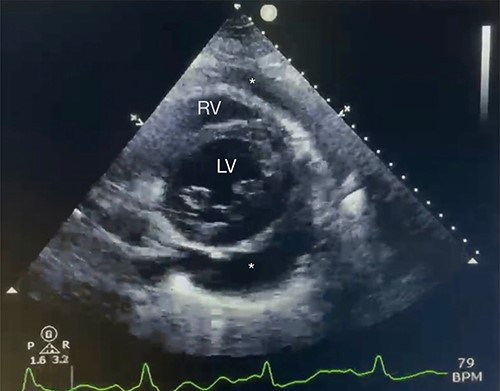

A 43-year-old woman with hypothyroidism and left lower extremity sarcoma that was treated with wide excision, and chemoradiotherapy treated with Doxorubicin, was performing routine screening with the oncologist which included a positron emission tomography/computed tomography (CT) scan, in which two small hypermetabolic nodules in the right upper lobe of the lung and a moderate to large pericardial effusion were found, effusion confirmed with an echocardiogram (Fig. 1). Upon findings, patient was sent to ER due to high suspicion of metastasis due to sarcoma history. She denied cough, shortness of breath, chest pain, palpitation, syncope or diaphoresis and related unintentional weight loss of 30 pounds in the last 3 months. Upon evaluation, patient was found with stable signs and there were no findings of pericardial tamponade. Chest CT scan was sent for further evaluation (Fig. 2).

Echocardiography with moderate pericardial effusion: subcostal 2 chamber echocardiography view demonstrating * = pericardial effusion, RV = right ventricle and LV = left ventricle.